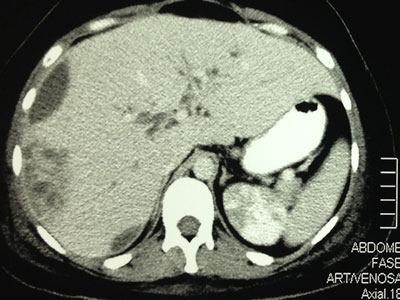

RM do Abdome Superior

Exames Complementares

Cultura de secreção do abscesso (28/05/2013): E. coli

Cultura de secreção do abscesso (28/05/2013): Escherichia coli

Abscesso Hepático Piogênico

- Patogênese: ocorre quando o inóculo da bactéria excede a capacidade do fígado de eliminá-la;

- Invasão de tecido -> infiltração de netrófilos e formação de abscesso organizado;

- Obstrução Biliar -> estase de bile -> colonização e infecção bacteriana -> ascensão fígado;